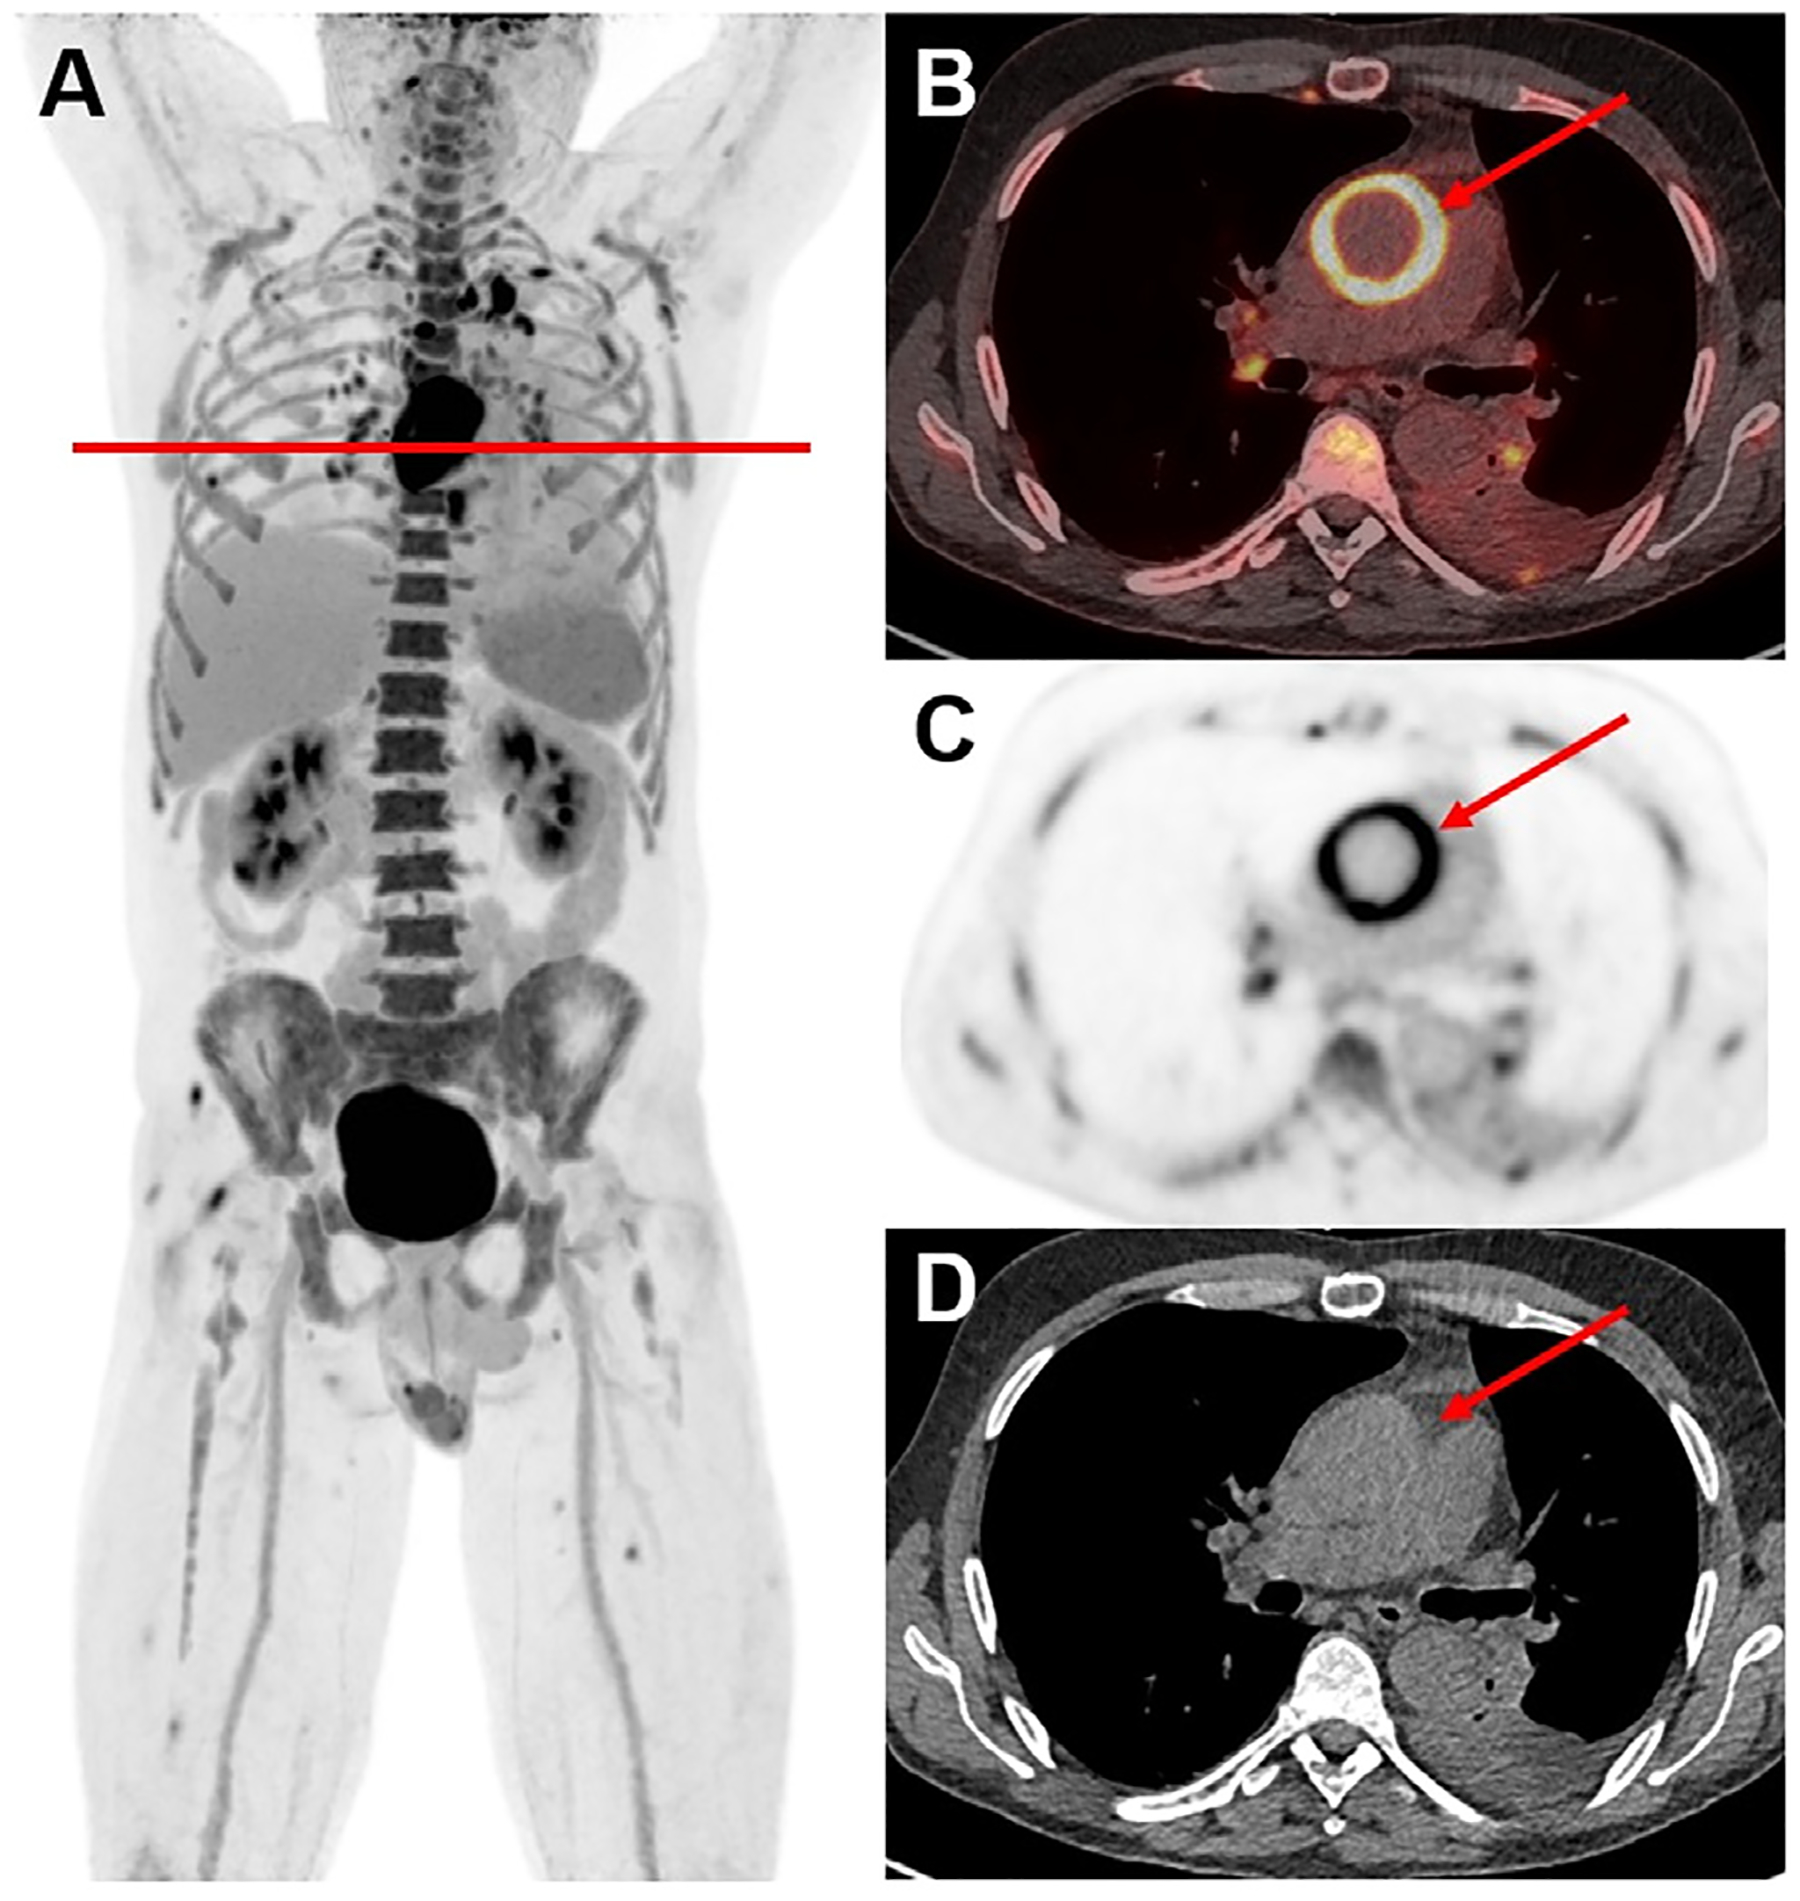

Inflammatory disorders historically have been difficult to monitor with conventional PET imaging due to limitations including radiation exposure, lack of validated imaging biomarkers, low spatial resolution, and long acquisition durations. However, the recent development of long-axial field-of-view (LAFOV) PET/CT scanners may allow utilization of novel noninvasive biomarkers to diagnose, predict outcomes, and monitor therapeutic response of inflammatory conditions. LAFOV PET scanners can image most of the human body (if not the entire body) simultaneously in one bed position, with improved signal collection efficiency compared to conventional PET scanners. This allows for imaging with shorter acquisition durations, decreased injected radiotracer dose, prolonged uptake times, or a combination of any of these. In addition, LAFOV PET scanners enable whole-body dynamic imaging. Altogether, these intrinsically superior capabilities in assessing both local and systemic diseases, have allowed these scanners to make increasingly significant contributions to the assessment of inflammatory conditions. This review aims to further explore the role and benefits of LAFOV scanners for imaging various inflammatory conditions while addressing future developments and challenges faced by this technology.